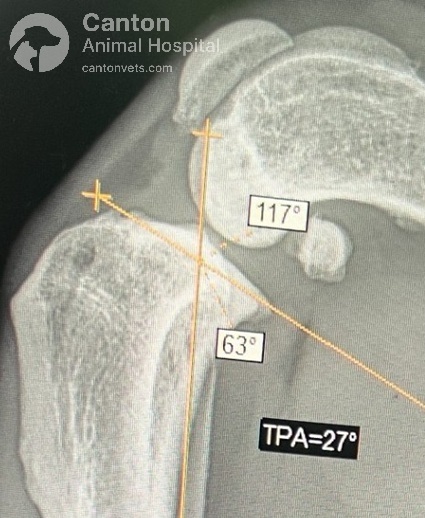

Tibial Plateau Leveling Osteotomy (TPLO) is a precise orthopedic procedure that requires detailed preoperative planning to achieve the best results. Before surgery, radiographs (X-rays) are taken to measure the dog's tibial plateau angle (TPA) and calculate the necessary rotation to achieve an optimal final angle of 5 to 6.5 degrees.

The proximal tibia (top of the shinbone) is carefully cut and rotated to change the slope of the tibial plateau.

A specialized bone plate is used to stabilize the osteotomy, ensuring proper healing.

By reducing the tibial plateau angle, the cranial tibial thrust is neutralized, allowing the dog to bear weight without abnormal joint movement.

Using a biradial saw blade, the proximal tibia fragment is rotated to the new TPA angle, calculated based on the patient’s individual measurements.